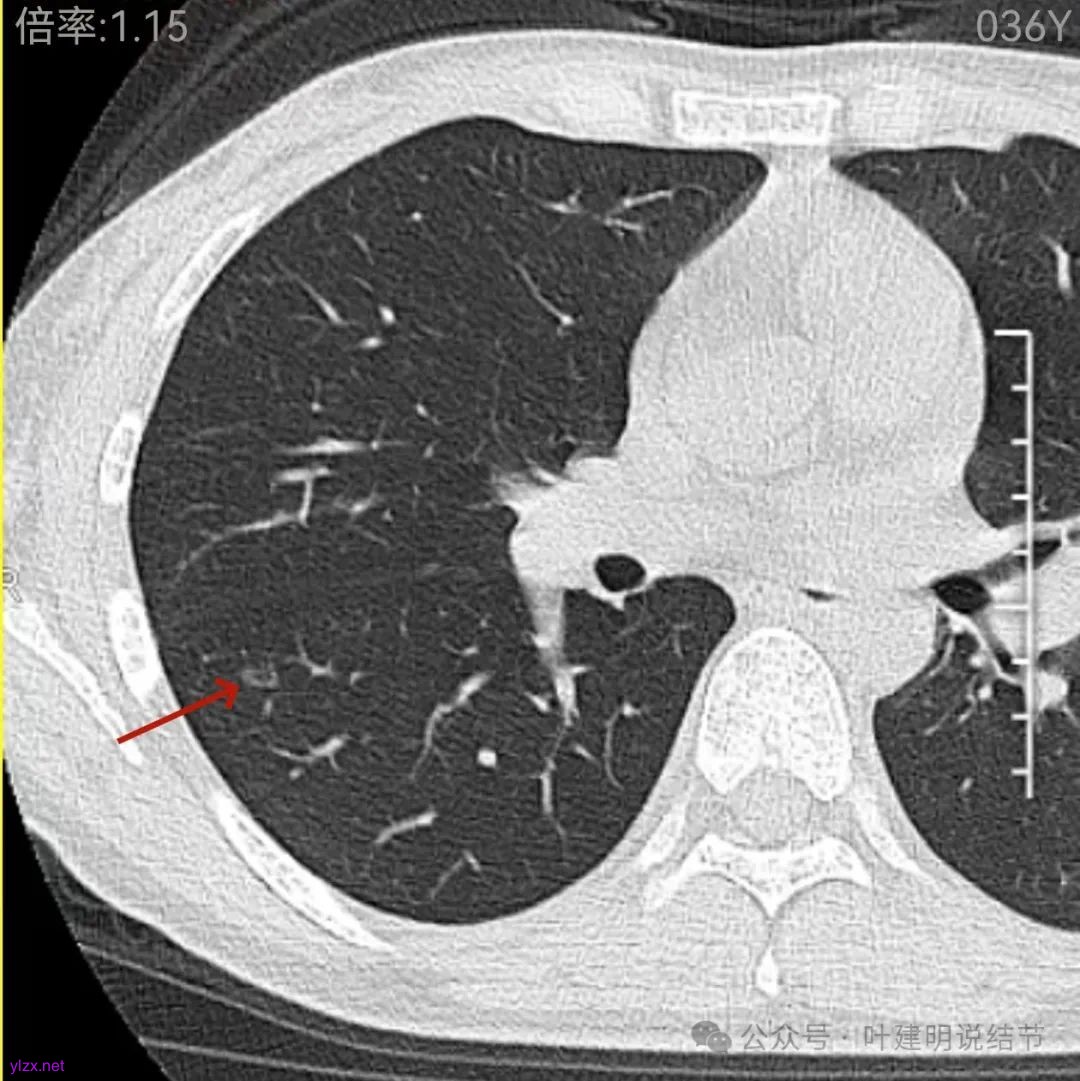

再看2022年9月的影像:

右下当时是很淡的,也显偏模糊的磨玻璃影。

怎么有个点状密度较高的结节在?与上面那截图的淡磨并不完全在一块的。

密度甚高,边界与轮廓清楚,只看这真的不像恶性些。

边缘区也瘤肺界限稍糊,整体轮廓还行。有进展的是不是就是淡磨那处?

两肺多发结节,左侧黄色标注的考虑是肺泡上皮增生可能性大;蓝色的考虑肺泡上皮增生或者少许慢性炎可能性大;右侧红色宽起来并带有红色箭头的这处是主病灶,偏混合密度,整体轮廓较为清楚,边缘显得毛糙,从2024年12月份的来看,要考虑是肿瘤范畴,原位癌或者微浸润性腺癌可能性较大,也不能完全排除不典型增生。但是在2022年的时候,这个病灶的边上也有一个实性的微小结节,如果只看2022年的,这么小的实性结节,又比较圆,表面也显得较为光滑,是要考虑良性的,当然太小了需要动态观察。回头再重新来看2024年底的,发现绿色箭头所指的这个微小实性的较2022年几乎没有变,去仔细寻找2022年的,发现当时在实性结节旁边也有密度很淡的一点磨玻璃影(也可能真的就是一处,只是扫描不够薄,密度的变化有些突兀而已),而到了2024年12月份,实性微小这处没有明显变化,但是原来很淡的磨玻璃变成了混合磨玻璃,范围也明显扩大。所以总体来看右肺下叶这处是考虑恶性的,而且从磨玻璃结节角度来讲,还是生长比较快的,就是说还是有一定风险的。加上左侧还有两处也是磨玻璃持续存在,虽然边缘轮廓显模糊一点,但多年以后也可能仍然要变成原位癌或者微浸润性腺癌之类的东西。通盘考虑以后,我倾向于右侧近期单孔胸腔镜下微创局部切除,左侧随访观察,等到有进展并风险增加再来考虑处理。意见供参考!